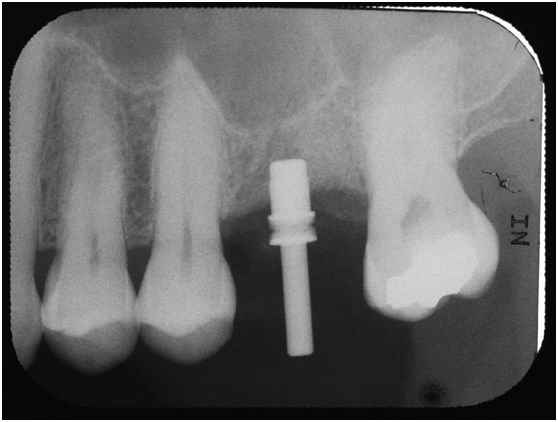

97/09/23 右下第一小臼齒植牙完成時

98/01/08經過三個半月做右下第一小臼齒的二階暴露,發覺鄰牙的植體高度竟已掉下來

a. 右下第一小臼齒的植體位置,放置得太低;若能將此顆植體上的polished surface放在骨平面上,應可減少之後將鄰近植體骨高度往下帶的情形。

b. 近遠心間距在植體間的間距需求為2-3 mm(指最終第一小臼齒植體與鄰近植體間距),比當初第一小臼齒尚未拔除時,是自然牙與植體的間距需求更大(最少為1.5mm);因此造成骨破壞的因素之一,也可能和鄰近植體的間距不足有關。